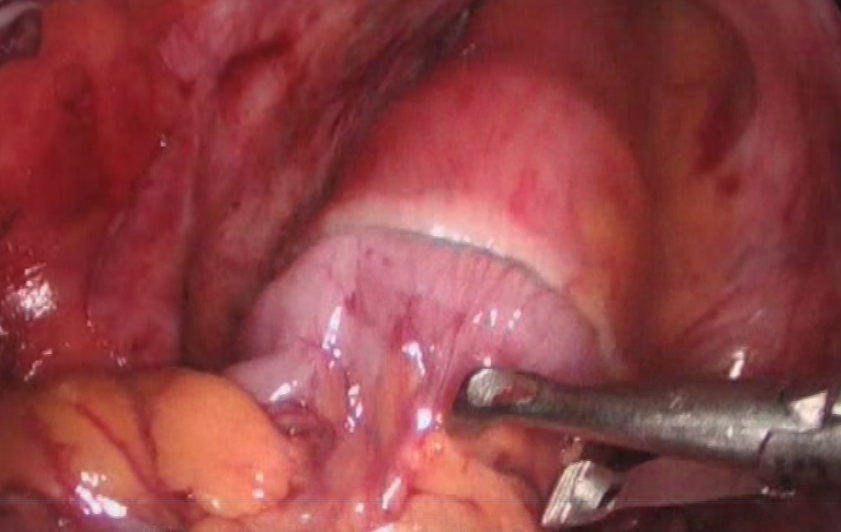

高龄直肠癌性梗阻处理的体会

结直肠癌是我国常见的恶性肿瘤,患者就诊时多已为晚期或局部晚期。由于肿瘤瘤体巨大,侵犯邻近脏器,多个脏器受累,临床处理有一定困难。部分外科医生面对晚期结直肠癌时选择放弃手术。但事实上,多学科综合治疗能使晚期或局部晚期患者获得相对好的治疗结果,不应该轻易放弃合理的外科手术。对于肿瘤巨大但没有远处转移,有多脏器受累的患者,直接手术切除困难,可以考虑进行术前的辅助治疗。外科手术原则是在能够达到R0切除的基础上,尽量保留脏器的功能,进行合理的区域淋巴结清扫。

这老太太87岁,肠癌梗阻,病情较晚,在其他医院不敢做,准备放弃了,来我院经过处理后,微创手术解决问题。